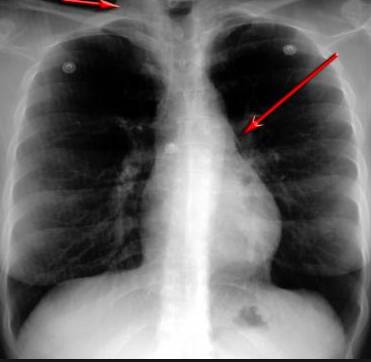

并且,因?yàn)楹粑到y(tǒng)結(jié)構(gòu)復(fù)雜,在體檢時(shí)醫(yī)生很難通過一種檢測手段,判定早期患者的病情。

使用這臺(tái)掃描儀,將直接把器官變成3D圖形!細(xì)微的毛細(xì)血管,幾毫米大的肺泡和支氣管,都將能看的一清二楚!

你的每一個(gè)氣泡,每一段支氣管,哪兒有病變都清清楚楚的將展示在醫(yī)生面前!

也就是說在一切都還沒開始惡化前,把這些有問題的器官組織都暴露的一清二楚:

沒有這項(xiàng)新技術(shù),醫(yī)生在做體檢的時(shí)候,很難通過一種測試斷定一個(gè)人是否有呼吸系統(tǒng)疾病。

可是現(xiàn)在他們不但能看到整個(gè)肺部的3維結(jié)構(gòu)圖。還能看到空氣進(jìn)入人體后的所有微小變動(dòng)!